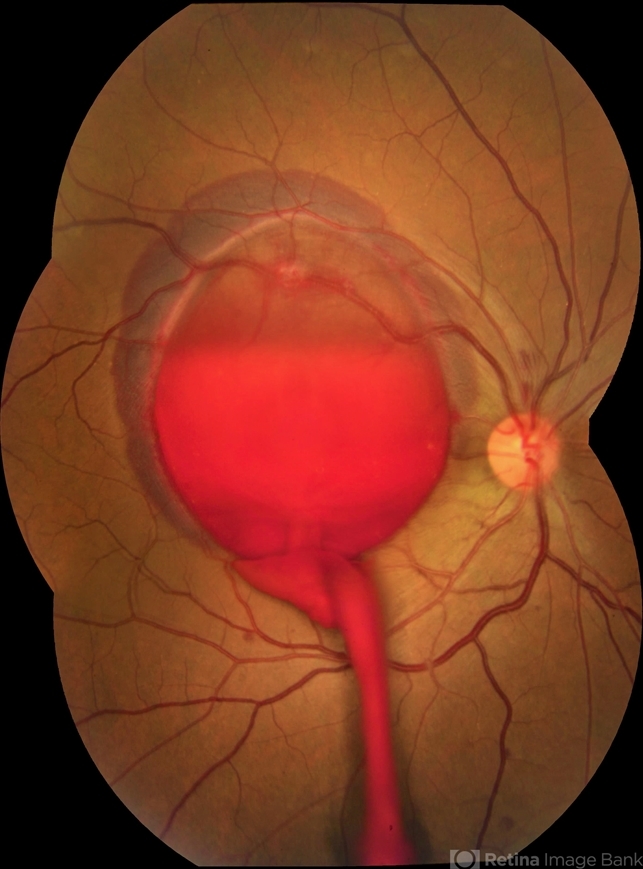

- valsalva retinopathy

- JEFFERSON R SOUSA - Study Center and Ophthalmological Research Dr. Andre M V Gomes, Institute Dr. Suel Abujamra São Paulo-Brazil

Fundus camera

Topcon TRC-50 DX, Imaginet, campo de 35 graus. Flash 36 / Mosaic with three images. - Description

- Male patient, 23-years-old, with low visual acuity in the right eye. In the ocular examination of the retinography, intense subhyaloidal hemorrhage. 1 minute after laser application.